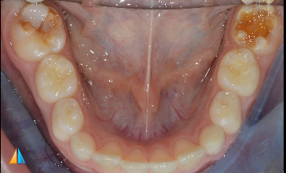

PEB on #16